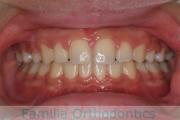

No.19V-044

- 主な症状:

- 上顎前突

- 年齢:

- 13歳

- 性別:

- 女性

- 抜歯部位

- 上:

- 44

- 下:

- 8558

- 主な使用装置:

- FEA

- 治療にかかった費用:

- 85万円

出っ歯を治したいということで小学生の時に来院されました。中学生になるまで経過観察をして、診断、上下左右から小臼歯を抜歯してマルチブラケット法にて治療を行いました。2年強、30回程度の通院が必要でした。

口元の突出感も大きく改善しています。

上下とも前歯の叢生(でこぼこ、凹凸、ガタガタ)がありましたので、保定をしっかりやらないと後戻りのリスクが出てきます。